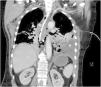

This is the case of a 67-year-old woman admitted to the ICU with refractory distributive shock. The thoracic x-ray (Fig. 1) revealed the presence of a left-sided hydropneumothorax, with a 5 cm apical pleural leave separation and contralateral mediastinal shift (⋆). The CAT scan performed (Fig. 2) revealed the presence of a hydropneumothorax and pleural empyema and periesophageal pneumomediastinum in the lower third of the esophagus (⋆). Thoracic drainage is performed, with the release of air and foul-smelling cloudy fluid containing "abundant bacteria, fat droplets, and fibers suggestive of food remnants." Upon suspicion of esophageal perforation, the new CAT scan performed with the administration of oral contrast (Fig. 3) reveals the presence of contrast extravasation at left lateral margin level of the lower esophagus, consistent with perforation, and contrast passage into the left pleural cavity (⋆). Emergency surgery is eventually performed.